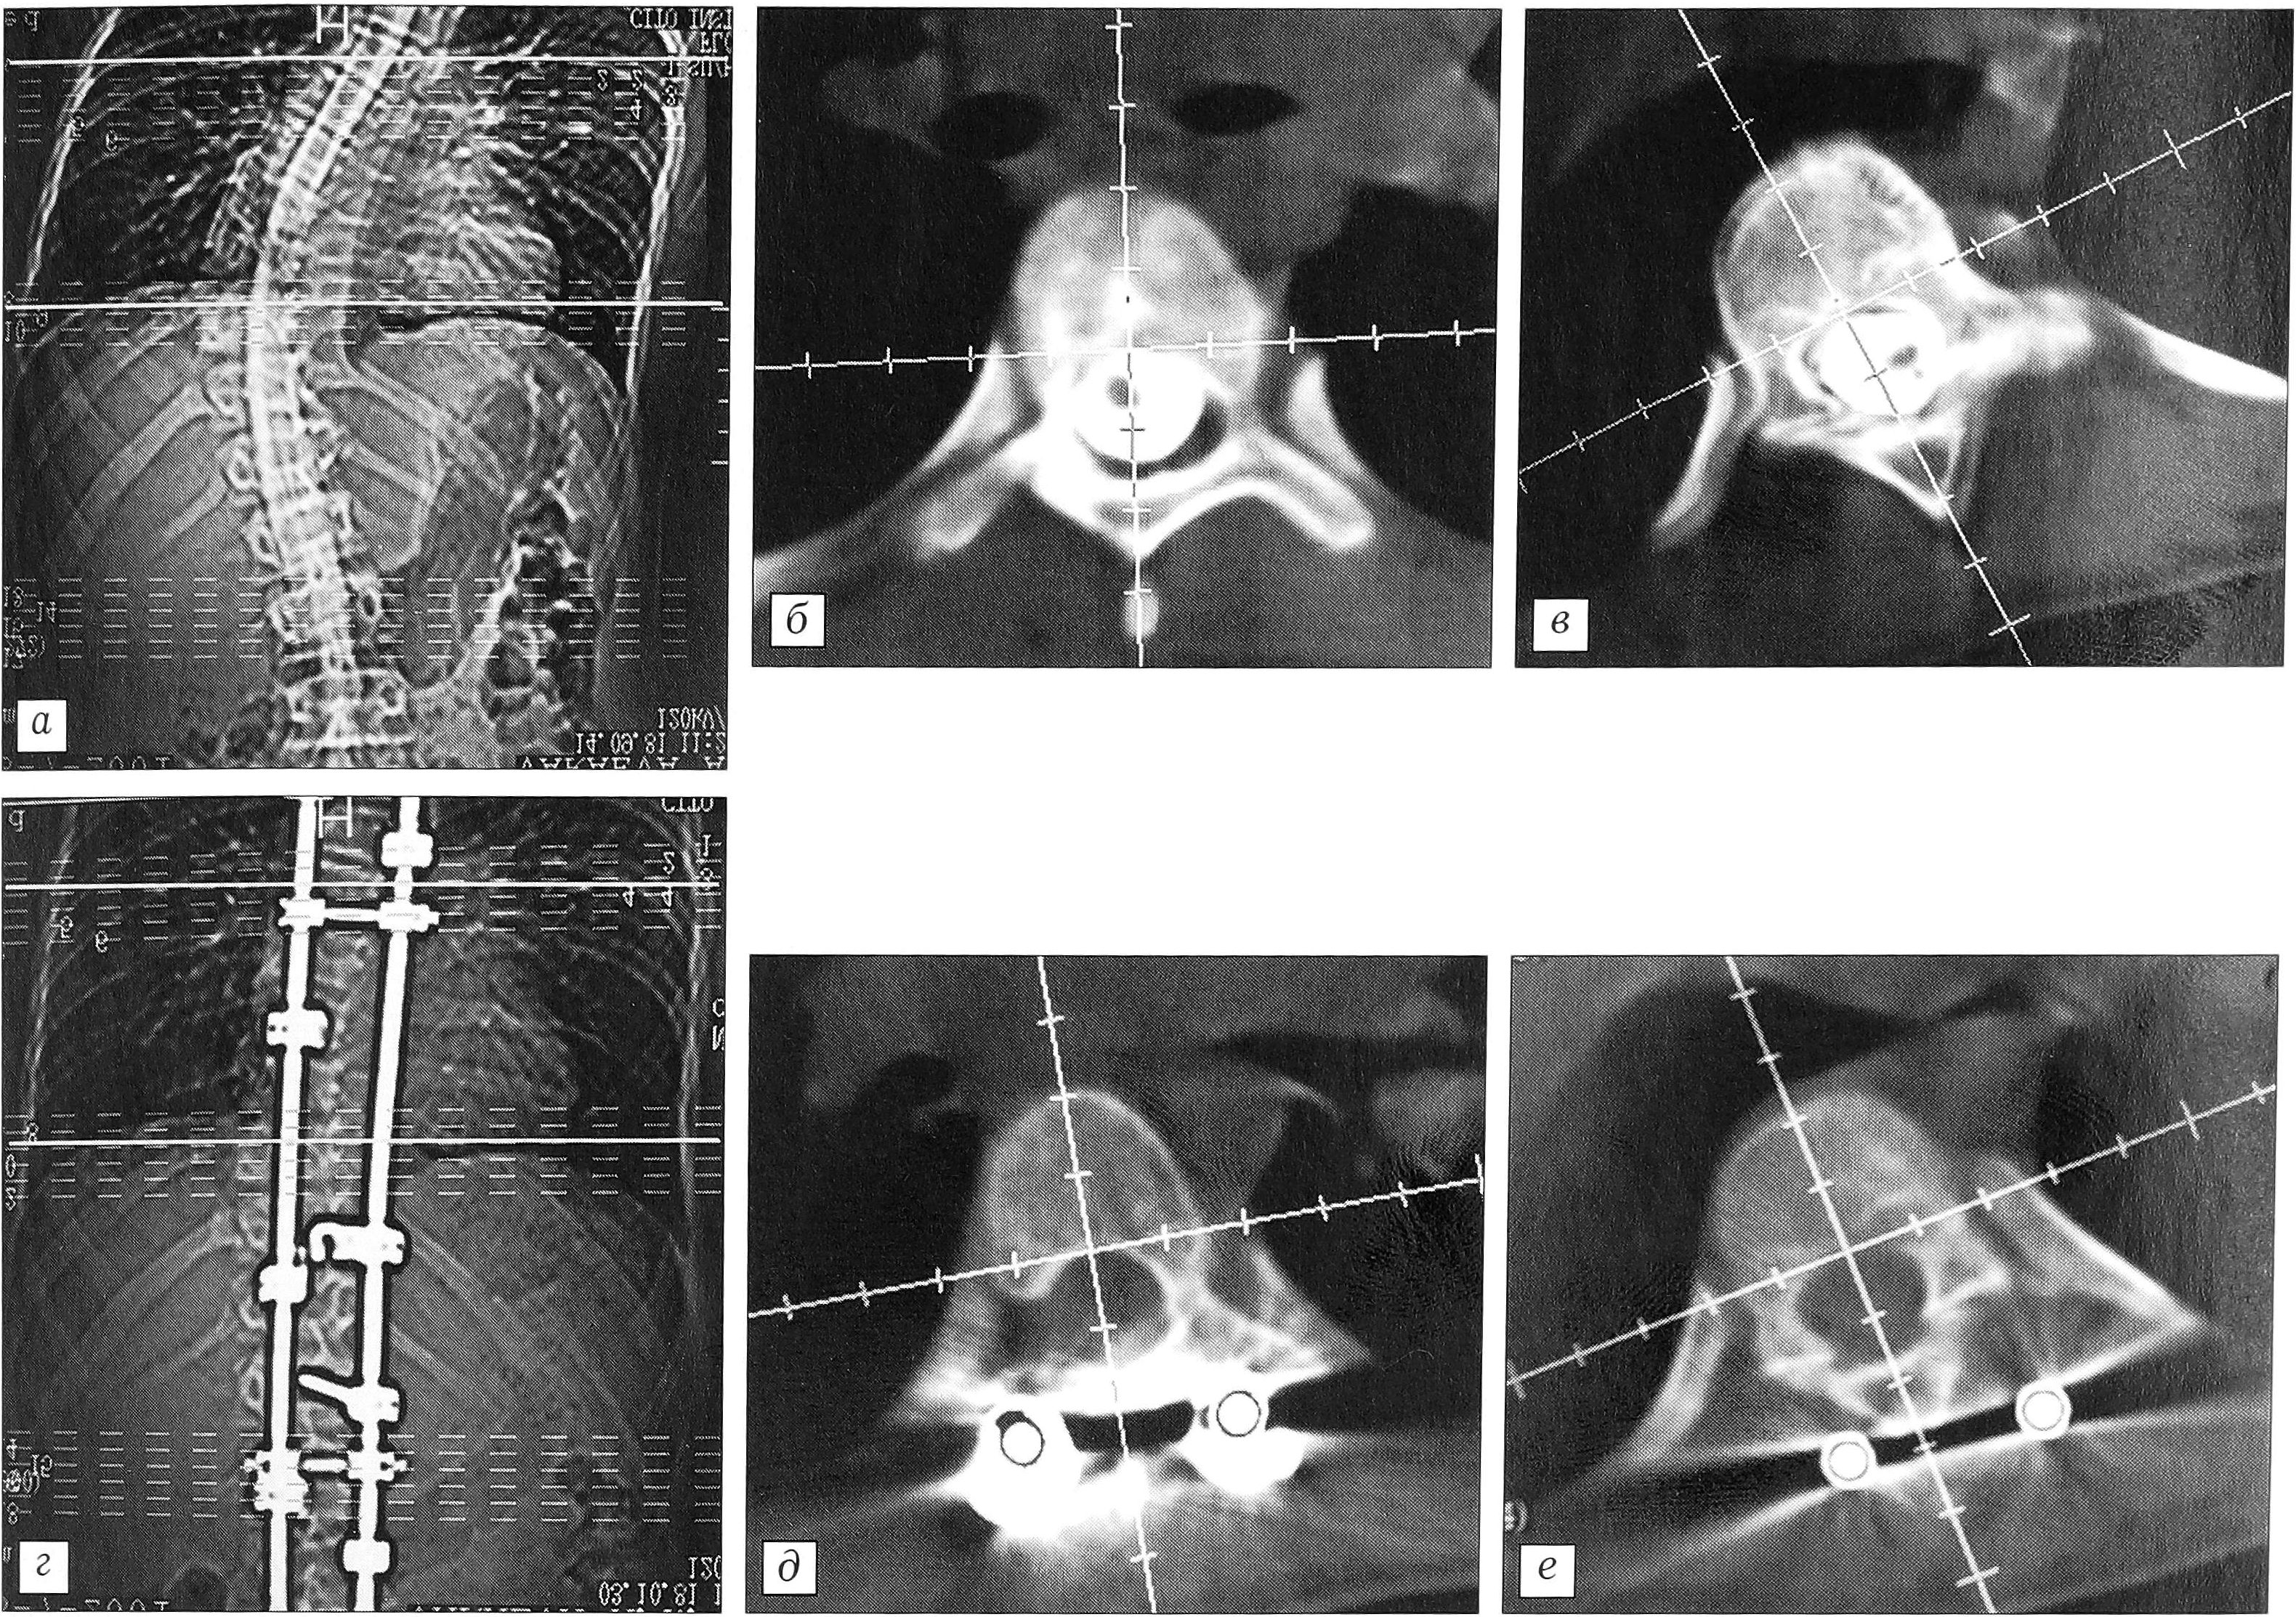

Нотация вершинного позвонка, измеренная относительно верхнего нейтрального, до операции равнялась в среднем 24,85°, т.е. была сравнима с абсолютной. После оперативного лечения она составила 18° — разница 6,85° (27,56%), что несколько больше соответствующего абсолютного показателя. В целом полученная коррекция ротации у каждого пациента несколько больше, поскольку верхний нейтральный позвонок, относительно которого проводятся измерения, также меняет свое положение в пространстве. В одном случае абсолютная деротация вершинного позвонка составила 5° (19%), а относительная — 11° (48,8%), что было связано с увеличением ротации вершинного позвонка на 6° (рис. 5).

Рис. 5. КТ больного В. с правосторонним грудным сколиозом до (а—в) и после (г—е) оперативного лечения. б, д — верхний нейтральный, в, е — вершинный позвонок.

Таким образом, проведенные исследования показали, что после оперативного лечения в большинстве случаев происходит деротация вершинного позвонка, но ее величина (3° — 12,2%) не является существенной и значимой. У 28% больных отмечено увеличение ротации после операции, однако во всех случаях (кроме одного, когда ротация возросла на 6°) оно было менее 5°, т.е. находилось в пределах ошибки метода исследования. Значимая деротация вершинного позвонка получена у 3 пациентов (14° — 33% от исходной ротации; 10° — 47,6%; 17° — 70,8%). Деротация вершинного позвонка, превышающая предел ошибки метода измерения (5°), констатирована у 31,8% пациентов.